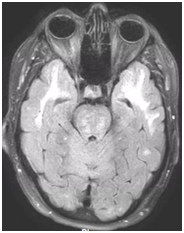

During follow-up in stroke clinic, her imaging was reviewed. MR imaging demonstrated large confluent areas of hyperintense T2 and FLAIR signal abnormality throughout the periventricular and deep white matter with extension into the subcortical white matter (Figure 1) (Figure 2). T1w images demonstrated low signal, corresponding to the T2/FLAIR abnormality on T2w images. This white matter abnormality is known as leukoaraiosis. The hyperintense T2/FLAIR signal abnormality also involved the anterior temporal lobes (Figure 3) (Figure 4) and external capsules (Figure 5) (Figure 6). This feature on MRI is uncharacteristic of other white matter diseases, notably the sporadic subcortical atherosclerotic encephalopathy. In our patient, the corpus callosum was spared. The lacunar infarcts were small vessel infarcts, typically seen in the deep white matter, basal ganglia, thalami, and the pons. On diffusion images, there was a small area of diffusion restriction in the left corona radiata that was consistent with an acute infarct (Figure 7) (Figure 8). Subsequently, there was an area of encephalomalacia on follow-up MRI at the location of the previous acute infarct. This abnormality correlated with the right-sided weakness seen prior to the index patient’s admission.

Figure 3 T2 axial image demonstrates hyperintense white matter signal involving the anterior temporal lobes on both sides.

Figure 4 FLAIR axial image demonstrates hyperintense signal in white matter in anterior temporal lobes, on both sides which is more conspicuously seen compared to T2 signal seen on Figure 3.

The white matter signal abnormality is nonspecific and seen in many diseases. However, the involvement of the anterior temporal lobes (86%) and external capsules (93%) is specific to suggest the diagnosis of CADASIL in appropriate clinical settings.8,9 CADASIL is a rare entity, its clinical features are nonspecific, and it is almost never considered as a leading differential at first presentation. However, MRI findings are relatively specific in the early course of the disease. MRI helps to rule out large territory infarctions and major intracranial or neck vessel occlusions. It also differentiates other conditions such as mitochondrialencephalopathy and stroke like episodes (MELAS), migraine disorders, and demyelinating disease like multiple sclerosis. Early involvement of the anterior temporal lobes and external capsules is characteristic in the initial stages of CADASIL. As the disease progresses, there is involvement of the white matter, which can also be seen with advanced demyelinating disease and microangiopathy. Hence, radiologists should be aware of the characteristic MR findings and clinical features as it guides the clinician to genetic testing for the specific diagnosis of the CADASIL.10